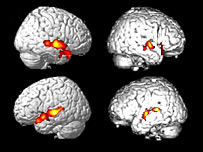

| | | همان بخش هايی از مغز بيمار (راست) فعال شد که در يک داوطلب سالم (چپ) فعال می شود |

گروهی از دانشمندان اروپايی می گويند تحقيقات تازه آنها به روی بيماری که قادر به حرکت کردن يا سخن گفتن نيست نشان می دهد که او می تواند دستورات شفاهی را درک کرده و از طريق تفکر به آنها واکنش نشان دهد. در اين مطالعه مغز يک زن 23 ساله که در يک تصادف رانندگی دچار جراحت شديد مغزی شد و در وضعيت نباتی (بيدار اما نه هوشيار) قرار دارد اسکن شد. محققان پنج ماه پس از تصادف، که در ژوئيه 2005 روی داد، با استفاده از "اف ام آر آی" که نوعی تصويربرداری مغناطيسی است مغز اين خانم را اسکن کردند. از اين خانم خواسته شد خود را درحال بازی تنيس تصور کند. اسکن نشان داد بخش هايی از مغز که به جنبش بازوها و پاها ارتباط دارد فعال می شود. اين دقيقا همان بخش هايی از مغز بود که در داوطلبان سالم فعال می شود. دکتر آدريان اوئن، متخصص اعصاب در شورای پژوهش های پزشکی در دانشگاه کمبريج و يکی از دست اندرکاران اين مطالعه گفت اين ثابت می کند که بيمار می تواند بشنود و تصميم گرفته است از طريق تفکر فعالانه به آن واکنش نشان دهد. اين شيوه اسکن می تواند به پزشکان کمک کند بفهمند آيا ساير بيمارانی که در وضعيت نباتی قرار دارند نيز می توانند فکر کنند يا نه. با اين حال محققان هشدار دادند که اين تنها ممکن است يک مورد منحصر به فرد باشد. اما اين يافته ها به جنجال های مربوط به سرنوشت افرادی که در وضعيت نباتی هستند و اجازه مرگ بعضی از آنها از طريق قطع تغذيه داده شده است دامن خواهد زد. نتايج اين مطالعه تازه در مجله "ساينس" چاپ شده است. |